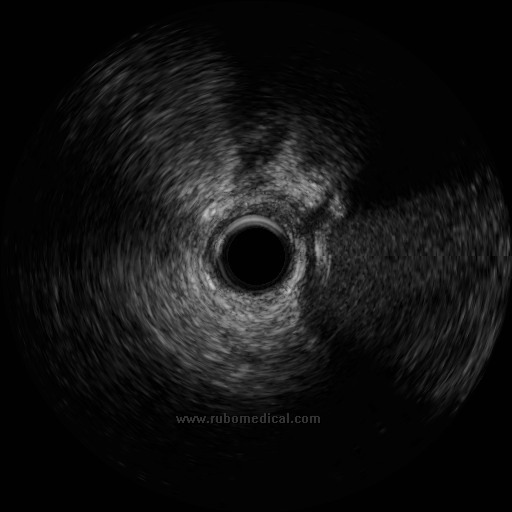

IVUS Navigated in Side

Branch to Resolve ambiguity

Case : CTO of Ostial LAD

IVUS in Side branch

LCX coming in

Ostial LAD

结合IVUS图像确认穿刺点及穿刺方向

• “葫芦”样或“8字”样特征:

• IVUS显示分支与主支的血管中膜层汇合的特征图像,分支与主支直径的突然变化